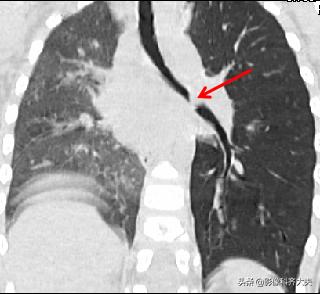

病例6、病史:女,两岁,吃花生时喝水引起呛咳。

轴位显示左侧支气管疑似异物,红色箭头。

冠状位重建清晰显示左侧支气管异物,红色箭头所示。

最小密度投影显示的更加清楚。